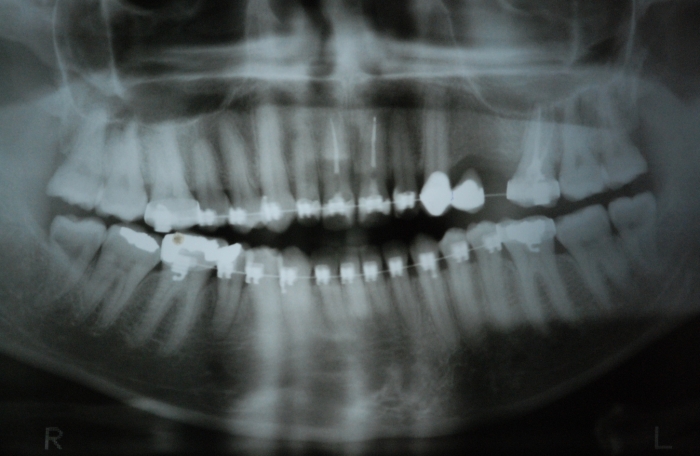

Rx mostrando a ausência de dois pré molares superiores